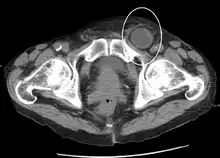

في تشخيص الفتق في البطن، التصوير هو الوسيلة الرئيسية لكشف الفتق الداخلية الفتق حجابي وغيرها، أو ان لم تكن متوقعة أو مشتبة في وجودها. الاشعة المقطعة ذات المجسات المتعددة (MDCT) يمكن أن تظهر على وجه الدقة موقع تشريحي للكيس الفتق، محتويات الكيس، واى مضاعفات. كما يقدم تفاصيل واضحة عن جدار البطن مما يتيح التعرف إلى أن جدار الفتق بدقة.[5]

يحدث الفتق الفخذي أسفل الرباط الإربي، عندما تمر محتويات البطن عبر منطقة ضعيفة في الجدار الخلفي للقناة الفخذية. ويمكن أن يكون من الصعب تمييزها عن الفتق الإربي (خصوصاً عند الصعود رأسياً): ومع ذلك، فإنه عموماً يبدو أكثر دائريةً، وعلى النقيض من الفتق الإربي، هناك كثرة في شيوع الفتق الفخذي لدى الإناث. حالات الاختناق في الفتق الفخذي عالية. تقنيات الإصلاح بشكل عام متشابهة في حالتي الفتق الفخذي والفتق الإربي.

إلى حد بعيد الفتق الأكثر شيوعا (ما يصل إلى 75 ٪ من جميع الفتق البطني) هو ما يسمى بالفتق الإربي. ويتطلب للفهم مزيد من المعرفة لأجل تشريح القناة الاربية. وتقسم أنواع الفتق الإربي إلى نوعين النوع الأول وهو الأكثر شيوعا (مصور هنا 2/3) هو النوع غير المباشر وهو يحدث نتيجة ضعف في الفتحة الأربية الداخلية الخاصة بالقناة الاربية، والنوع الثاني هو الفتق الإربي المباشر (1/3)، وهنا تضغظ محتويات الفتق على الجدار الخلفى للقناة الأربية. الفتق الإربي هو النوع الأكثر شيوعا في كل من الرجل والمرأة. ولكن الفتق الفخذي يحدث في كثير من الأحيان في النساء أكثر من الرجال، ولكن النساء تصاب بالفتق الإربي أكثر من الفتق الفخذي.